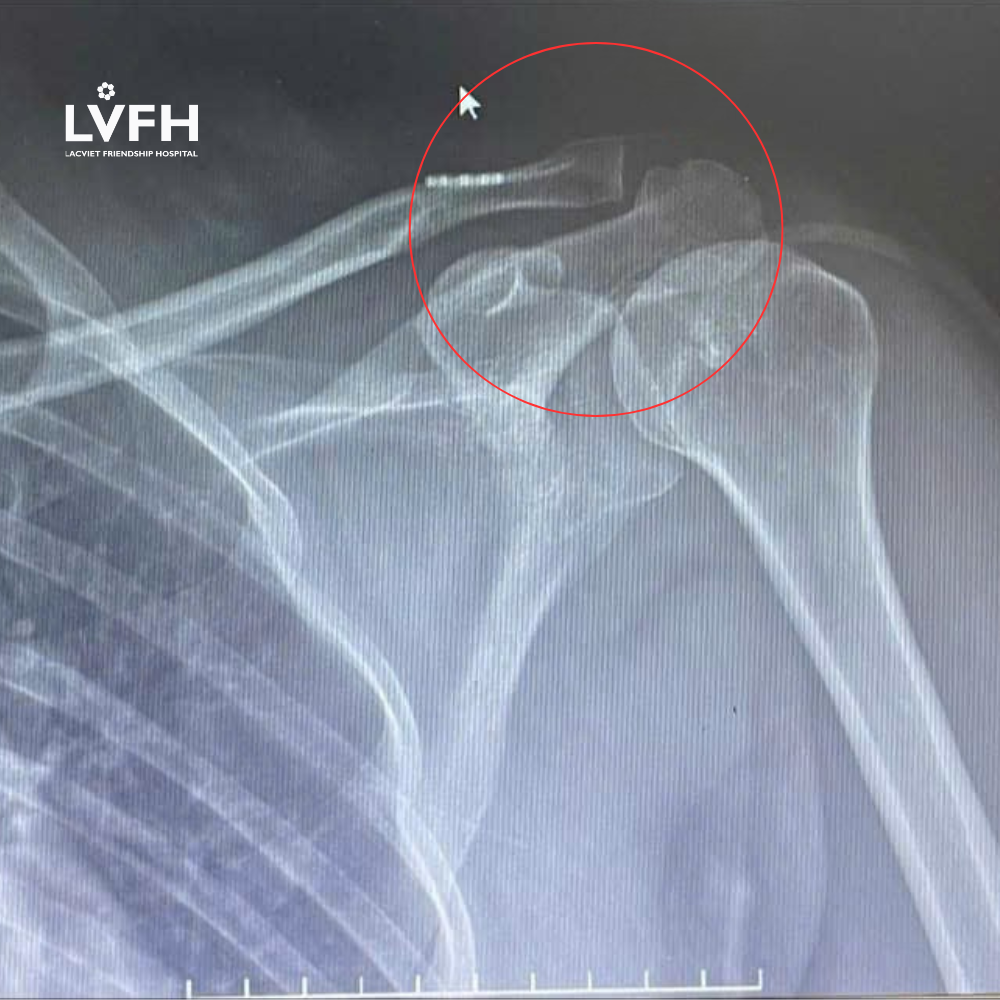

Bệnh nhân nữ, 43 tuổi, có tiền sử tai nạn giao thông cách nhập viện 3 tuần, được chẩn đoán chấn thương cột sống, xẹp đốt sống L3 và trật khớp cùng đòn trái. Sau khi điều trị bảo tồn ổn định cột sống, người bệnh vẫn còn đau nhiều vùng khớp vai trái.

- Khớp cùng đòn trở lại vị trí bình thường